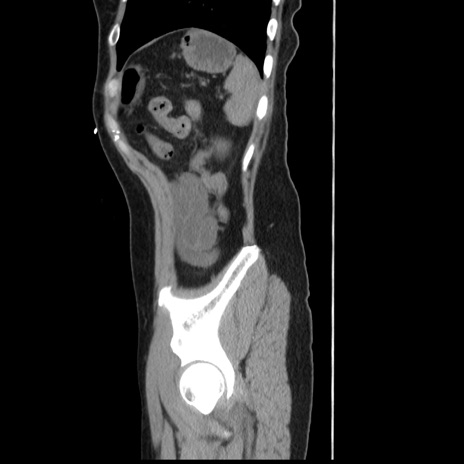

症例10(矢状断像)

【症例】 50歳代女性

【主訴】 腹痛

【現病歴】前日生レバーを食べた。今朝に排便あり。 昼前に突然発症の腹痛を生じ、当院救急外来を受診した。

【既往歴】 子宮筋腫にてで子宮全摘後

【身体所見】 意識清明、腹部:平坦、軟、下腹部やや左を中心に圧痛・反跳痛あり、筋性防御あり

【データ】WBC 7800、CRP 0.07